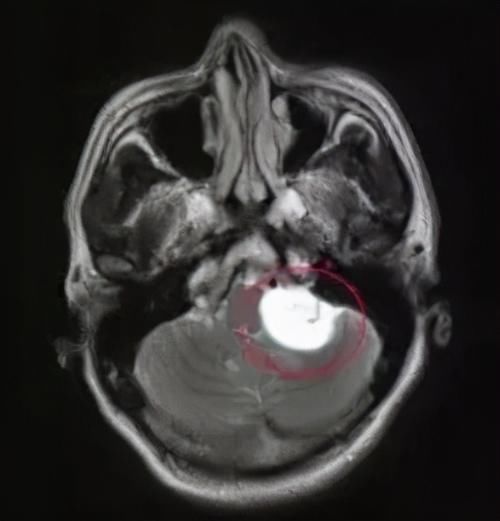

作为大脑的疾病,下丘脑错构瘤的确诊首选方案是核磁共振检查。

在核磁共振检查当中可以看到明显的肿瘤生长在下丘脑附近。

文章插图

无奈之下,父母把他带到了医院,经过各学科的专家会诊,发现他下丘脑旁边有一个7毫米的错构瘤。

最终,他的诊断也很明确了,就是下丘脑错构瘤导致的痴笑发作。